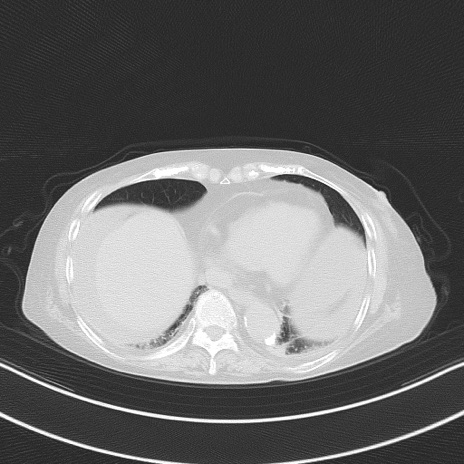

他院CT